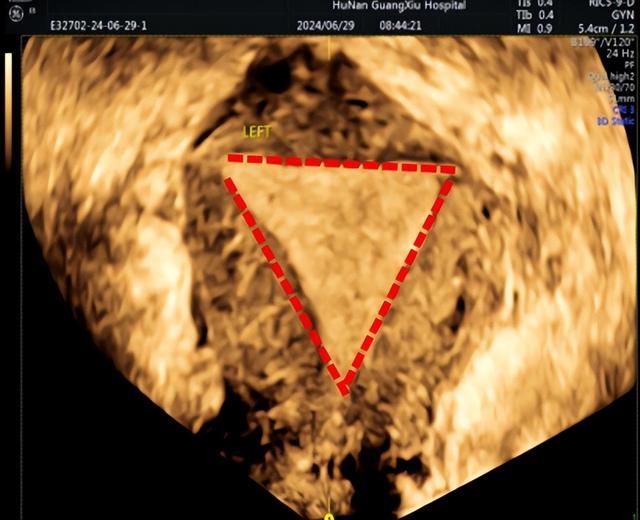

下图是正常宫腔,呈倒置三角形态。

而在下面这张图我们可以看到:宫腔失去了正常倒三角的形态,下段宫腔因为粘连导致缩窄呈窄桶状。